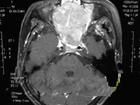

圖1 腦內脊索瘤成年患者有長期頭痛病史並出現一側展神經麻痹者,應考慮到脊索瘤的可能但確定診斷尚需藉助X線、CT和MRI等影像學檢查。

3.MRI:腫瘤多為長T1長T2信號,瘤內囊變區呈更長T1長T2信號,鈣化為黑色無信號影,出血灶則呈高信號注射Gd-DTPA後腫瘤輕度至中度強化(圖1)。